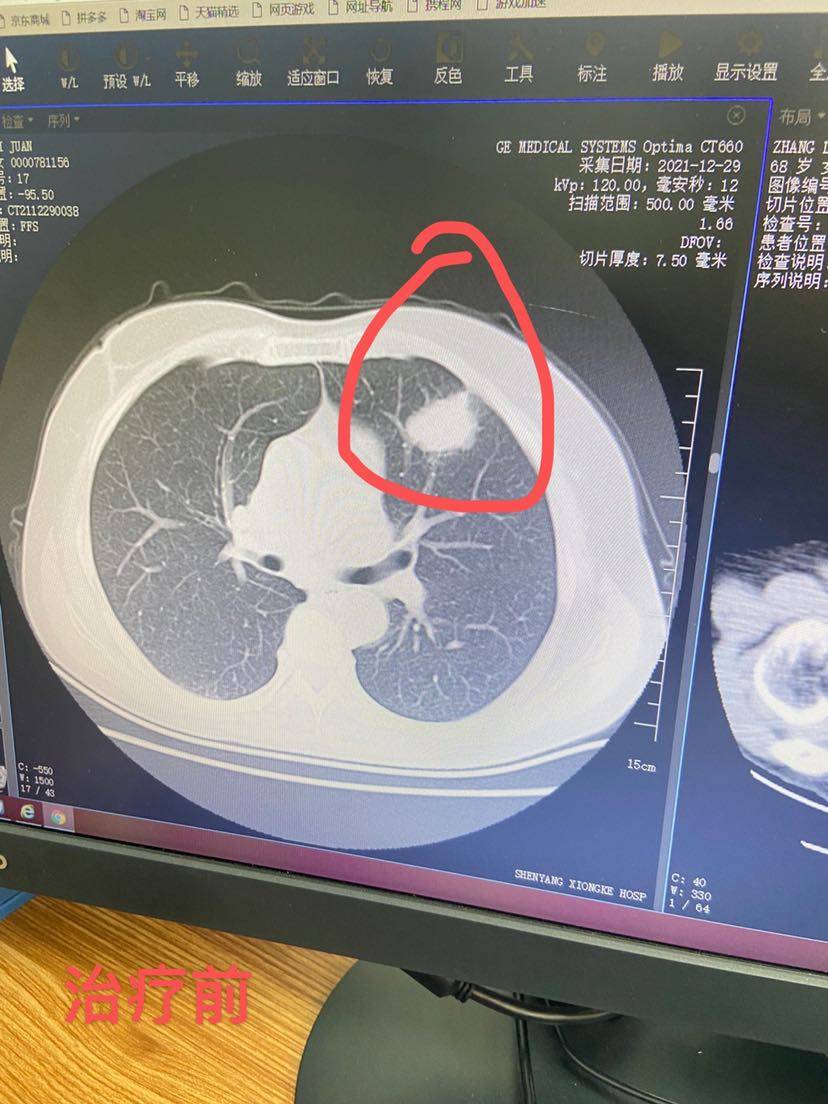

这次治疗之前也是第二次复查,结果很满意,在停药期间依然能有这么好的效果!

八点入院,去主任办公室交流近期患者情况,了解这次复查的结果,目前处于停药阶段效果最好的就是我家患者,其它病友不同程度的缩小和进展,但是都很少,不影响这次用药,开好住院单,输液第五个疗程的免疫药,与临床老师提交记录数据、领取第六个疗程的安罗替尼,用完药准备回家!